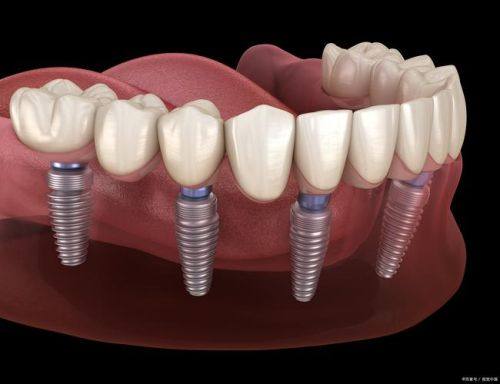

虽然种植牙不能用医疗保险报销,但了解其费用构成和影响因素,能让患者更好地规划自己的支出。种植牙的费用主要包括种植体的费用、基台的费用、牙冠的费用以及手术费用和检查费用等。种植体的品牌和材质是影响费用的重要因素,不同的品牌和材质价格差异较大。例如,进口的高端种植体价格可能会比国产的种植体高出特别多。牙冠的材料也有多种选择,如烤瓷牙冠、全瓷牙冠等,全瓷牙冠相对来说价格会更贵一些。此外,患者的口腔状况也会影响费用,如果患者口腔存在炎症、骨量不足等问题,可能需要精良行相应的治疗,这也会增加整体的费用。